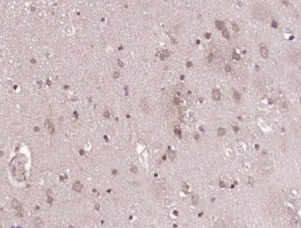

多聚甲醛固定,石蜡包埋(人脑胶质瘤);用柠檬酸钠缓冲液(pH6.0)煮沸15min后恢复抗原;用3%过氧化氢阻断内源性过氧化物酶20分钟;阻断缓冲液(正常山羊血清)37℃30min;用(B7 H6)聚电解质进行抗体孵育未结合的克隆抗体在1:400下在4°C下过夜,然后根据SP试剂盒(兔子)说明和DAB染色进行操作。